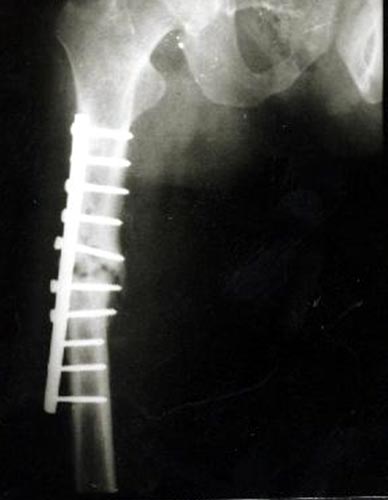

病例四、患者男性,13岁,股骨干中远1/3骨母细胞瘤,切除瘤体后形成大段骨缺损。我们用髓内钉和钢板内固定,大段异体骨植骨,骨生长因子和骨髓细胞的植入,骨缺损在12个月顺利愈合。